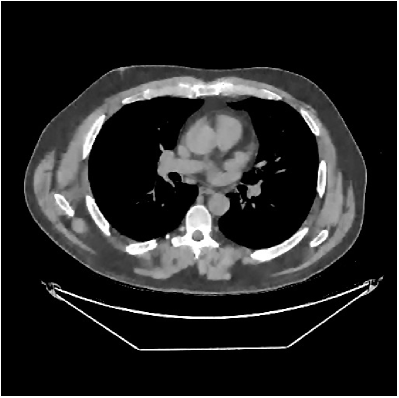

| views | ||||

|---|---|---|---|---|

| (a) , | (b) , | (c) , | (d) , |

Fig. 7 studies the influence of regularization parameters and on PWLS-ST-. Given a fixed hard-shrinkage parameter , a larger value better removes noise (or unwanted artifacts), but too large can oversmooth reconstructed images; compare Fig. 7(a) and Fig. 7(b). Given a fixed regularization parameter , a larger value leads to lower sparsity in sparse codes and achieves better noise reduction, but too large can remove some edges (e.g., in bone regions); compare Fig. 7(c) and Fig. 7(d). In particular, Fig. S.8 in the supplement shows that once the value is properly chosen, PWLS-ST- is robust to a wide range of values.